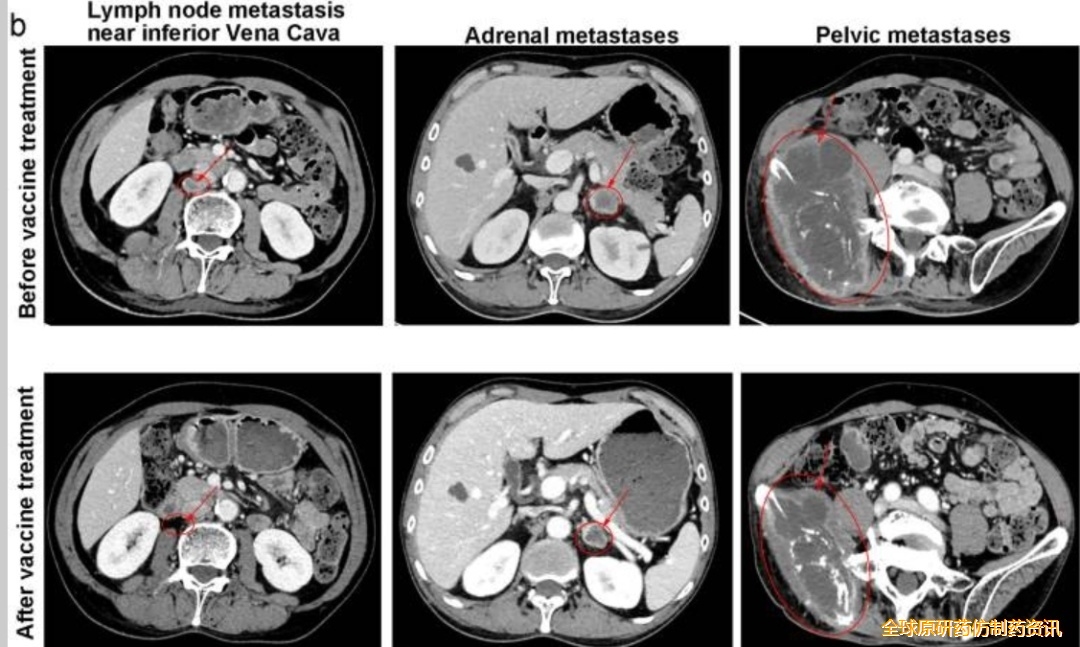

这位幸运的患者既往接受三线化疗和放疗均失败,但在使用 Neo-DCVac 后 7.6 个月内未出现任何疾病进展迹象。在五剂个性化Neo -DCVac 免疫治疗之前和之后进行 CT 扫描显示肿瘤靶病灶显著消退。

这位患者同样也经历三线化疗、放疗和 PD-1 抑制剂治疗失败,在 Neo-DCVac 治疗后,肿瘤靶病灶缩小了 29%。